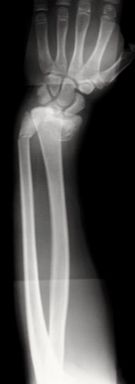

Las fracturas desplazadas o inestables precisarán de reducción cerrada o abierta en quirófano, asociado en algunos casos a osteosíntesis (Figura 10). Las fracturas localizadas en la unión metafiso-diafisaria distal son inestables y en muchos caos requieren tratamiento quirúrgico (Figura 11).

Figura 10: a, b-Fractura de radio y cúbito distal inestable en paciente de 12 años. c- Reducción y estabilización mediante agujas de Kirschner. c-Control final al año de la cirugía.